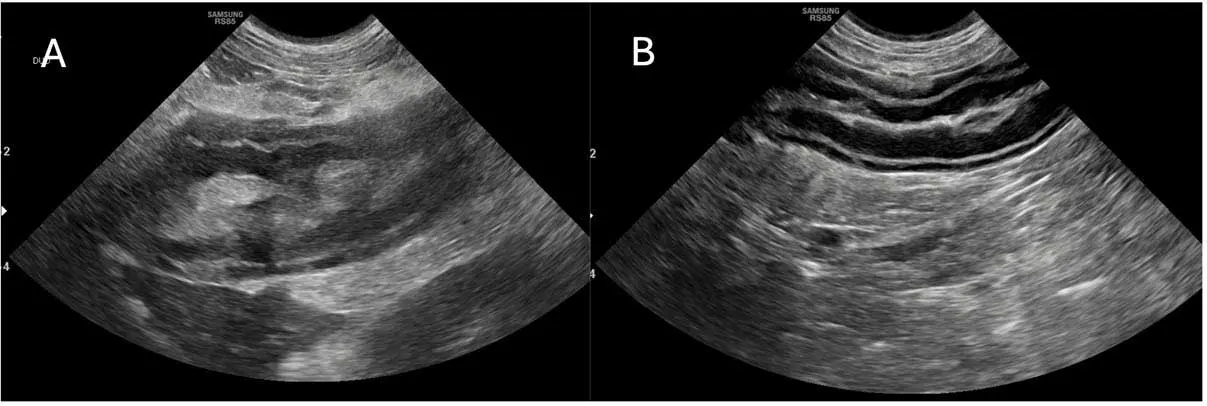

The bottom line is that AUS does not allow for the 100% confirmation or exclusion of CAP. Studies have suggested sensitivity of 70% to 88% for ultrasonographic changes, sometimes dependent on the criteria used21,40,42,43,49. Suggested criteria are identification of at least two highly suggestive changes: pancreatomegaly, pancreatic hypoechogenicity, pancreatic heterogenous echogenicity, hyperechoic mesentery (potentially the most commonly reported at 82% to 83%) and peripancreatic free fluid16,20,36,49,50. Potentially suggestive, but less important, signs are corrugated adjacent duodenum/colon, pancreatic cysts/abscesses, venous thrombosis, biliary/pancreatic duct dilation, thickening of the gastric/duodenal wall and signs of ileus36. Strong evidence exists that AUS findings change over time and may lag behind disease progression, as cPLI activity appears to increase first36,39. In two studies, at time of admission 12 out of 38 (32%) and 24 out of 37 (65%) dogs had at least two highly suggestive signs of CAP, but a further 12 out of 38 and 10 out of 37 (who mostly had no changes at all on admission) developed these after two to three days, for a total sensitivity of 68% to 92%36,39. Therefore, for dogs where CAP diagnosis is not clear but still suspected, repeating AUS after two to three days may be of significant aid (Figure 2).

As well as pancreatic changes, CAP can also be associated with changes to the local GI tract. Forty-seven % of dogs with CAP have GI wall changes, most commonly to the duodenum (71%; Figure 3)16.